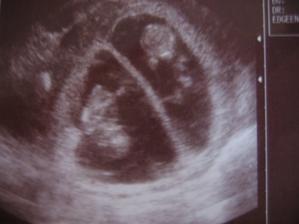

Zda sa ze nase 1. a snad aj posledne ICSI s PK sa podarilo🙂

Onedlho nás uvidíte ako malé bodky na sone,

Či budeme dve, či jedno, to je v rukách vyššej moci,